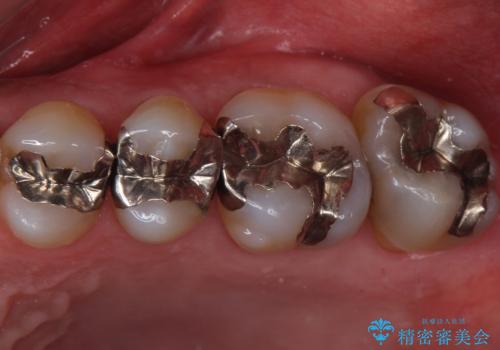

奥歯の虫歯 ゴールドインレーでの修復処置

- メンテナンスで3年ぶりにいらっしゃた患者様です。

検査の結果虫歯が確認されたため、治療を進めることとなりました。

- 左上7 ゴールドインレー 77,000円費用は治療当時の料金となります